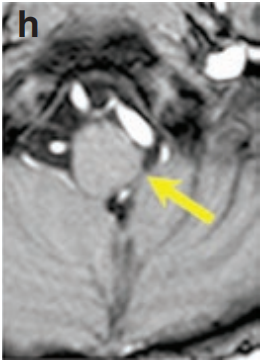

病例中的男婴Nick最初表现为头部持续左倾、眼球外展受限以及反复喉炎发作。MRI检查显示左侧延髓存在胶质瘤并伴有扩展性生长。

经过全面评估,患儿父母最终选择由INC巴特朗菲教授主刀手术。手术在术中磁共振和神经电生理监测双重保障下进行,采用俯卧位肿瘤全切术。术中影像确认肿瘤完全切除,无残留病灶。

通过枕后正中开颅入路,术中使用CUSA刀切除肿瘤。在左侧延髓外侧隐窝处发现肿瘤与后组颅神经粘连,通过精细分离成功保留颅神经功能,特别注重保护吞咽功能相关的第九、十、十一对颅神经。

术后两周患儿恢复良好,长期随访显示术后三年MRI复查无肿瘤复发迹象。患儿神经功能完好,健康成长。